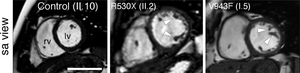

Building on the earlier study, the team led by Dr. José Luis de la Pompa aimed to analyze the specific mechanisms that make Mib1 so important for the correct development of the heart. For this analysis, the team used CRISPR-Cas9 molecular-scissor technology to insert the LVNC-causing mutations into the mouse genome.

Analysis of these mouse models showed that the animals developed LVNC only if they carried two allelic copies of one of the Mib1 mutations. As Dr. De la Pompa explained, “this differs from the situation in patients, who manifest the disease in the presence of a single copy of one of the MIB1 mutants. In addition to this, the mice developed heart valve defects, either alone or in combination with LVNC.”

The team verified the data in mouse models. “When we simultaneously introduced the set of mutations identified in one of the two LVNC families, the mice developed heart chamber defects, leading to an LVNC-like disease and affecting heart function. In contrast, the set of mutations from the other family caused valve defects, showing that the additional variants function as modifiers of the effect of the Mindbomb1 mutation,” explained Marcos Siguero Álvarez.